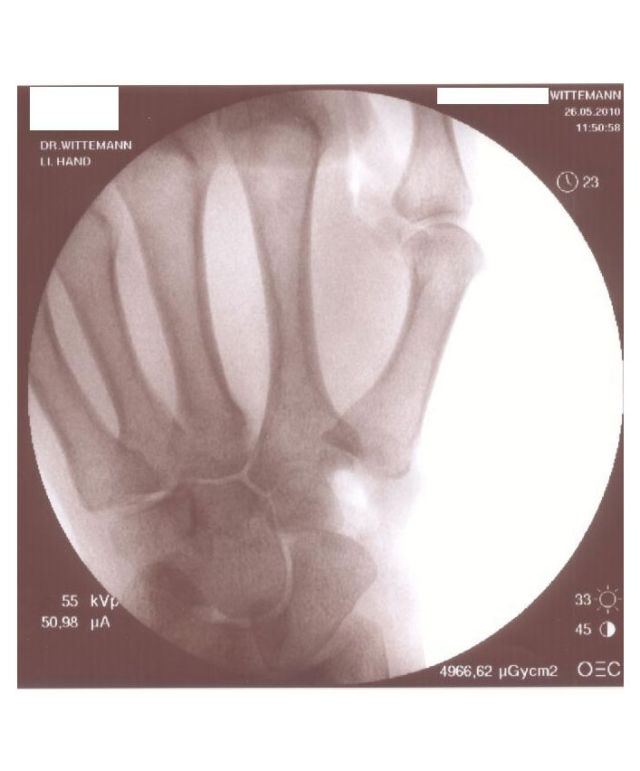

Im Anfangsstadium, wenn zwar die typischen Symptome vorliegen, aber auf dem Röntgenbild noch keine Veränderungen erkennbar sind, ist es sinnvoll unter Röntgendurchleuchtung Kortison in das Sattelgelenk zu spritzen. Diese Injektion soll bewirken, dass die im Rahmen der Arthrose entzündete und geschwollene Gelenkschleimhaut abschwillt und damit der Druck im Gelenk und der Schmerz reduziert wird.

Sollte diese Injektion keine oder keine ausreichende Wirkung zeigen oder die Wirkung hält nur kurz an, dann wäre als nächster Schritt die Arthroskopie (Gelenkspiegelung) des Sattelgelenkes erforderlich.